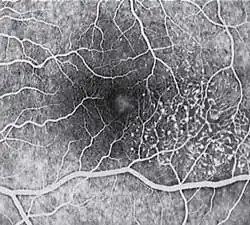

Diagnosis of MacTel type 2 may be aided by the use of advanced imaging techniques such as fluorescein angiography (which may identify an abnormal capillary pattern), fundus autofluorescence, and OCT. These can help to identify the abnormal vessels, pigment plaques, retinal crystals, foveal atrophy and intraretinal cavities associated with this disorder.

Areas of focal RPE hyperplasia (pigment plaques) often develop in the paramacular region as a response to these abnormal vessels. Other signs of macular telangiectasia type 2 include right angle venules, representing an unusual alteration of the vasculature in the paramacular area, with vessels taking an abrupt turn toward the macula as if being dragged.

Fluorescein angiography (FA) is helpful in identifying the anomalous vasculature, particularly in the early stages of Type 2 disease. Formerly, FA was essential in making a definitive diagnosis. However, the diagnosis can be established with less invasive imaging techniques such as Ocular Coherence Tomography (OCT) and fundus autofluorescence. Some clinicians argue that FA testing may be unnecessary when a diagnosis is apparent via less invasive means.